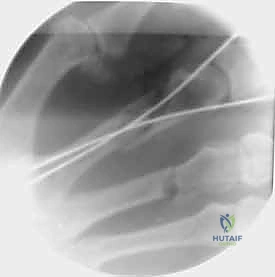

1. التثبيت باستخدام الأسلاك الدقيقة (K-wires)

تُعد هذه الطريقة (Percutaneous Pinning) من التقنيات طفيفة التوغل. يتم إدخال أسلاك معدنية رفيعة جداً عبر الجلد لتثبيت العظم المكسور تحت توجيه الأشعة السينية المستمرة (C-arm) داخل غرفة العمليات.

* الميزة: جروح صغيرة جداً، تعافٍ أسرع للأنسجة الرخوة.

* الإزالة: غالباً ما يتم إزالتها في العيادة بعد 4-6 أسابيع بدون الحاجة لتخدير كامل.

خطوات التثبيت الجراحي - توثيق بصري (Intraoperative Imaging)

يحرص الدكتور هطيف على توثيق خطوات العمل الجراحي لضمان أعلى مستويات الدقة. نستعرض هنا مجموعة من الصور من داخل غرفة العمليات توضح مدى تعقيد ودقة هذه الجراحات:

تتطلب الجراحة انتباهاً خاصاً للأوتار الباسطة والقابضة والأعصاب الدقيقة المحيطة بالعظام. استخدام تقنيات الجراحة الميكروسكوبية (Microsurgery) يضمن عدم الإضرار بهذه الأنسجة الحساسة.